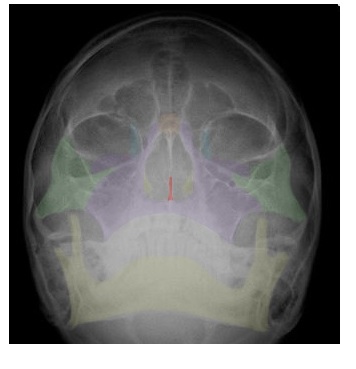

in red,  | VOMER |

| SPHENOID |

in yellow,  | ETHMOID |